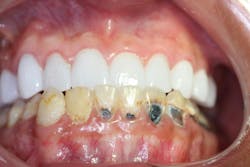

Patient: 24-year-old male with HbSS SCD, renal insufficiency, and frequent vaso-occlusive crises (figure 1)

Chief complaint: Pain, sensitivity, and desire for improved esthetics

Findings

- Rampant caries, pulpal involvement, enamel hypoplasia

- Gingival pallor and mild inflammation

- Facial esthetic concerns and malocclusion